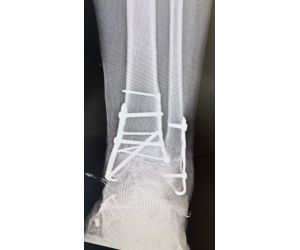

Ankle Fracture with Intercalary Fragments - Update

Maximilian Heitmann

Following up on my previous post that showed the preoperative CT slices. https://lnkd.in/e74BVTPn See also this previous case discussion...